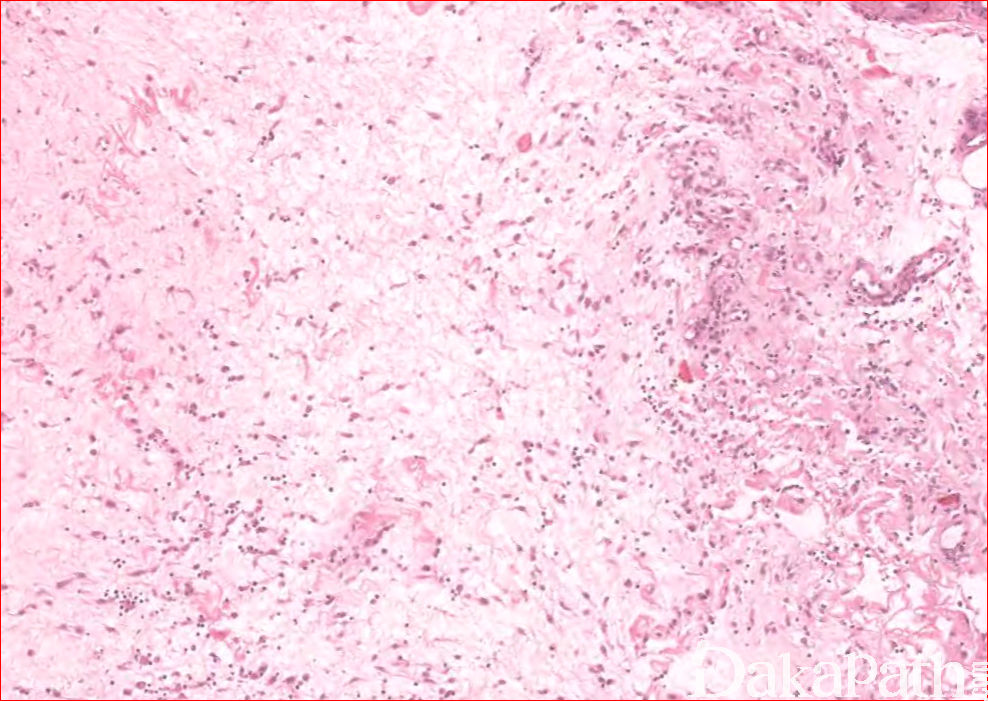

嗜酸细胞性筋膜炎

eosinophilic fasciitis